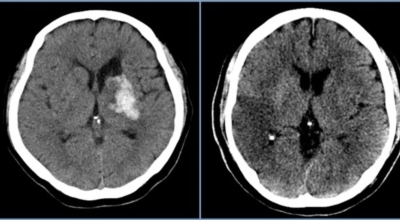

뇌경색의 경색이란 허혈성 괴사를 말해요. 여기서 허혈이란 혈관이 막히는 것을 말하고 괴사는 말 그대로 일부가 죽는 것을 말하는데 뇌경색의 경우 뇌의 혈관이 막혀 뇌세포 일부가 죽는 걸 의미해요. 뇌혈관이 막혔다 해서 혈액 공급이 안되는것은 또 아니에요.

막힌 혈관으로도 혈액이 공급되긴 하나 혈관이 막혀있어 혈액을 보내긴 하나 제대로 흐르지 못하고 혈액이 쌓이고 축적되어 물풍선에 물이 꽉 차서 터지듯 뇌혈관이 터지는 경우가 일어날 수 있는데 이를 뇌출혈 이라고 해요. 물론 외상으로 인한 뇌출혈도 있지만 이처럼 뇌경색으로 인해 혈관이 막혀 터지는 경우도 있어요.